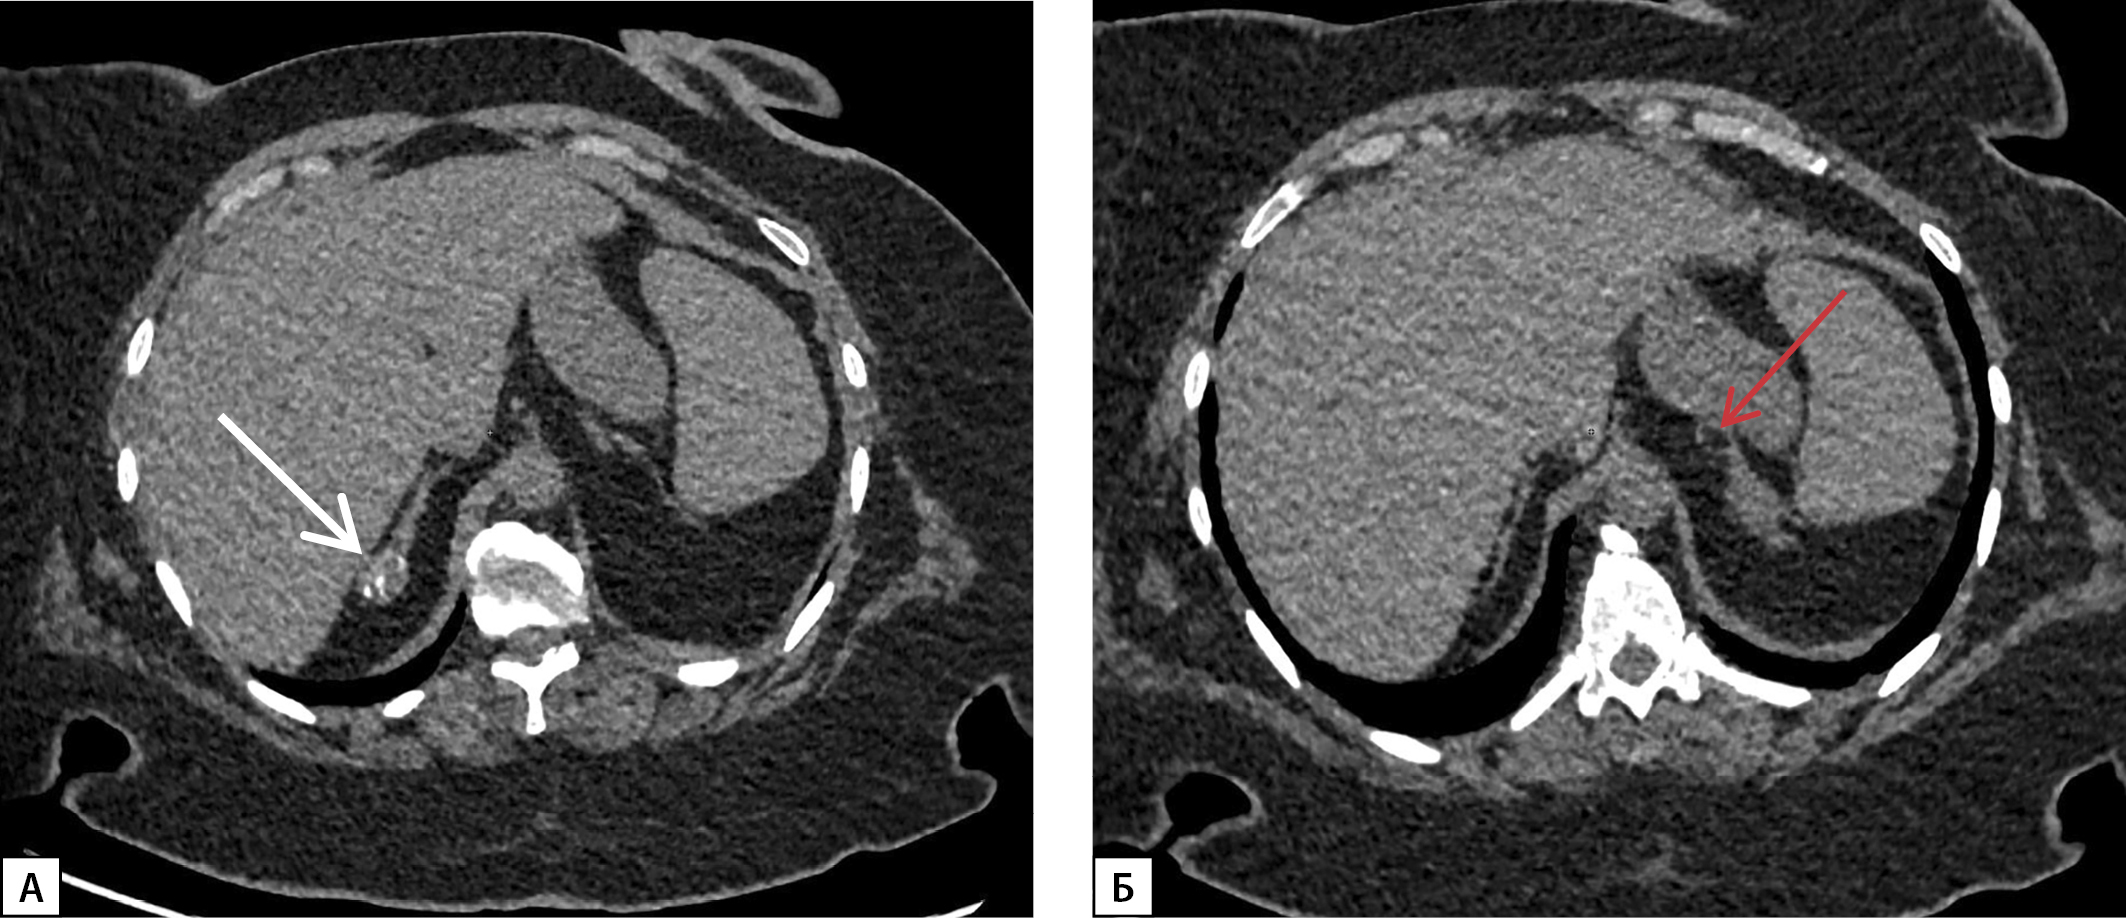

В 2005 г. впервые, по данным КТ надпочечников, диагностировали объемное образование размером 0,8–1,0 см слева. В последующем неоднократно выполняли КТ надпочечников для динамической оценки. На момент последней госпитализации в 2023 г., по данным МСКТ в динамике, в дистальных отделах латеральной и медиальной ножек правого надпочечника определялось образование размерами 25х19х20 мм округлой формы с ровными четкими контурами, наличием кальцинатов в структуре, неоднородной плотности от -4HU до 20HU в нативную фазу исследования, в теле левого надпочечника сохранялось образование жировой плотности (-108HU), с ровными четкими контурами, размерами до 17х12х16 мм. Данные образования трактованы как двусторонние миелолипомы небольшого размера (рис. 5).

Рисунок 5. МСКТ надпочечников, нативная фаза:

А — в дистальных отделах латеральной и медиальной ножек правого надпочечника образование округлой формы с ровными четкими контурами, наличием кальцинатов в структуре (белая стрелка); Б — в теле левого надпочечника образование жировой плотности, с ровными четкими контурами (красная стрелка).